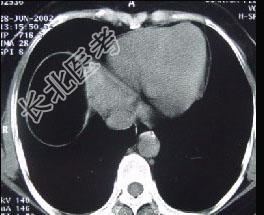

单项选择题男,30岁, 右下腹稍隆起,CT检查如图, 最可能的诊断为 ( )

A、右膈下脓肿

B、间位结肠

C、右膈下脂肪瘤

D、右下肺肺大疱

E、右下肺炎